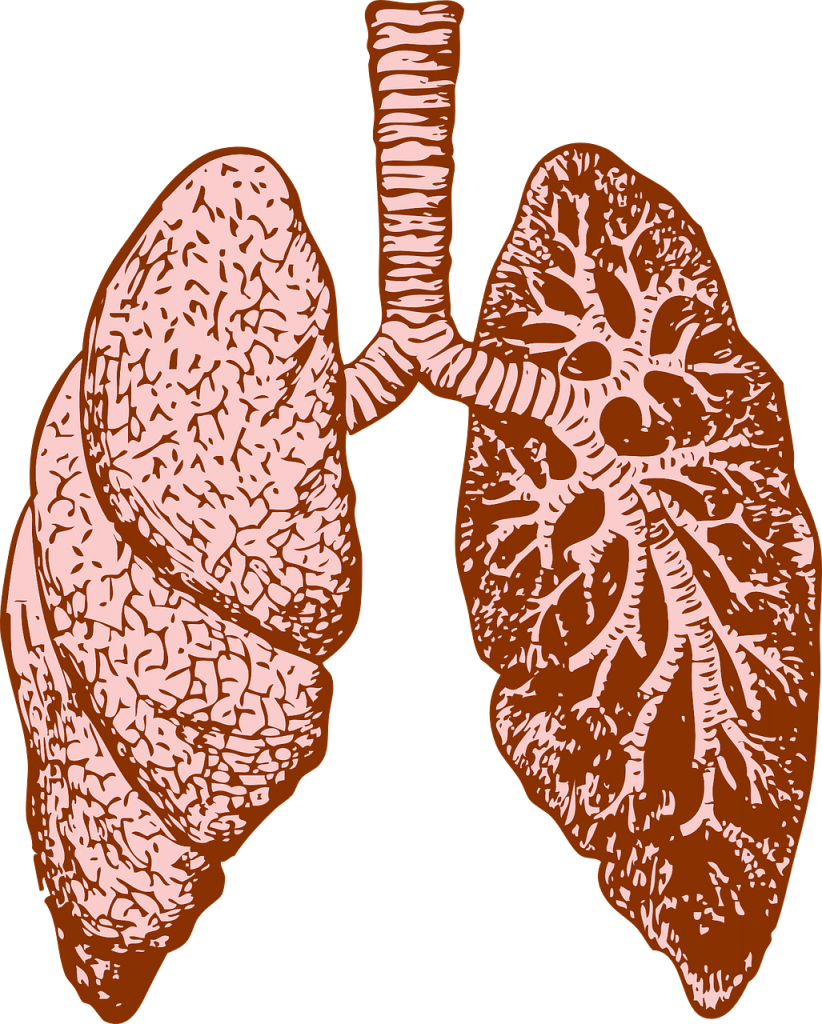

AKCİĞER

Nefes alıp-verme yoluyla temiz havanın vücut içine alınmasını ve kirli havanın vücut dışına atılmasını sağlayan organlardır. Akciğerler, göğüs kafesi içinde yer alan pembe renkli, süngerimsi görünüşte organlardır. Akciğerler, sağ ve sol olmak üzere iki bölümden oluşur. Sol taraftaki akciğer, hemen altında kalp bulunduğu için daha küçüktür.